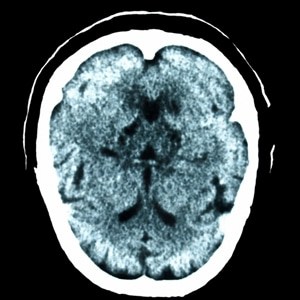

Multiple sclerosis is an autoimmune disease that affects the central nervous system.3 The immune system attacks myelin, a protective coating on the nerves, and the damage disrupts communication between the body and brain, causing those with MS to lose some control of balance and movement.4 Severe cases of MS can prevent sufferers from walking independently. The symptoms of multiple sclerosis are wide-ranging and can last for days, weeks or months at a time. Most people with MS experience symptoms for a duration of days or weeks and then can go months or even years before experiencing the symptoms again.5 These lengthy periods of remission are perhaps one of the most complicated aspects of the disease, as patients can never be entirely sure of when the symptoms will reappear. In most cases, relapsing-remitting MS eventually leads to a steady progression of symptoms with little or no period of remission.6 Some MS sufferers experience an onset of symptoms without relapses known as primary-progressive MS.7 Signs and symptoms of MS include:

Researchers followed 27 patients in a 24-week study, using MRIs to reach the conclusion that the Nintendo Wii balance board led to the development of white matter tracts that are linked to balance.8 Half of the subjects were tasked with using the Wii system five days a week for 30-40 minutes for three months, while the other half went without any intervention.9 Then the roles were reversed for another three months. The growth of the white matter tracts suggests that the Wii balance board is a viable means of physical rehabilitation for those with MS. Researchers believe this can benefit MS patients by reducing the risk of accidental falls.10 Perhaps the only downside of the study is the small sample size, but if more MS patients adopt the idea and see improved balance from the Nintendo Wii balance board system, the novel device could find an unexpected salutary purpose.